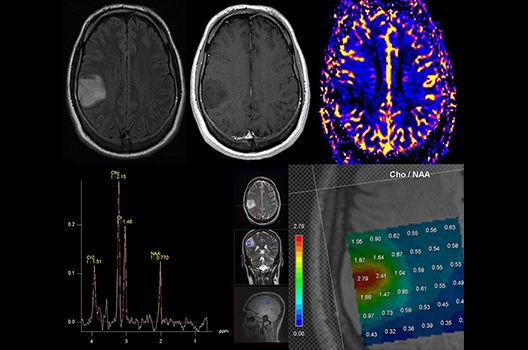

- MR-Protonenspektroskopie

Die Schwerpunkte in der MR-Forschung liegen in der multiparametrischen und funktionellen Bildgebung bei onkologischen und anderen, neuroradiologischen Fragestellungen und umfassen die Anwendung modernster MR-Verfahren sowie die Untersuchung an Hochfeld-Geräten.

Die Magnetresonanztomographie (MRT) ist ein Verfahren, bei dem durch magnetische Kräfte Bilder des Körperinneren angefertigt werden. In der Neuroradiologie können manchmal kleinste Veränderungen schwere Folgen haben; daher forschen wir an der Entwicklung hochauflösender MRT-Sequenzen, mit denen diese Prozesse und auch einzelne Nervenfaserbahnen sichtbar gemacht werden können. Darüber hinaus sind bei vielen Erkrankungen des Gehirns die Blutgefäße betroffen. Daher arbeiten wir an der Neu- und Weiterentwicklung von MRT-Sequenzen zur Darstellung der Blutgefäße und zur Blutflussanalyse (sog. „Angio-MRT“). Einen besonderen Forschungsschwerpunkt unserer Klinik stellen die MR-Protonenspektroskopie und die funktionelle MRT dar, mit denen die Analyse einzelner chemischer Substanzen im Hirngewebe oder die Darstellung ausgewählter Hirnfunktionen möglich ist.